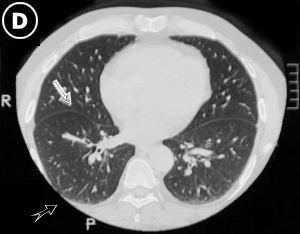

• Corte Tomográfico

nivel tercio medio del tórax.

hilear pulmonar

• Flecha Blanca: Cisura interlobar. Hileo pulmonar sin adenopatias.

• Flecha Negra: Borde pleural normal, sin colecciones o derrame pleural.